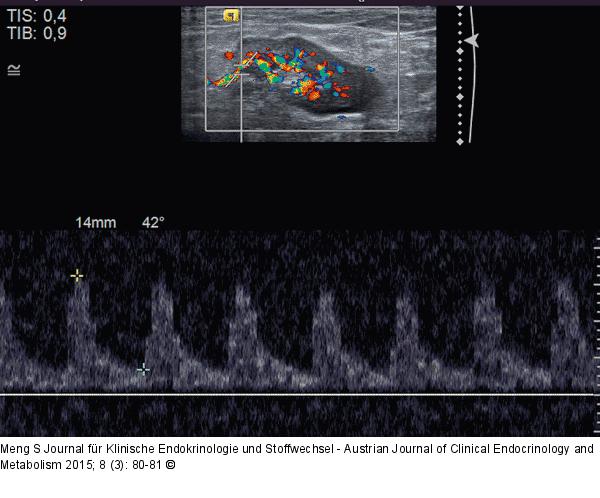

Abbildung 4: Lymphknoten-Ultraschall

PW-Doppler-Analyse. In der Literatur sind immer wieder Hinweise auf die Wichtigkeit der Analyse der Flusskurven intranodaler Arterien zu finden. Die relevanten Schwellenwerte für Resistance Index (RI) oder Pulsatilitätsindex (PI) schwanken in der Literatur stark. Prinzipiell sei bei pathologischen Lymphknoten mit einem eher hohen peripheren Widerstand mit entsprechenden RI und PI zu rechnen. An dieser Stelle seien dem geneigten Leser freie Gedanken zur zeitlichen Durchführbarkeit von Flussmessungen gegebenenfalls mehrerer Lymphknotenarterien mehrerer Lymphknoten mit den passenden Geräteeinstellungen innerhalb der täglichen Routine selbst überlassen. Lymphom. |